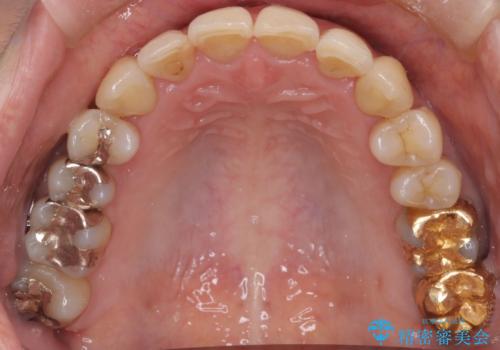

患者様にしっかりとインビザラインを使用して頂けたことで綺麗な仕上がりとなりました。